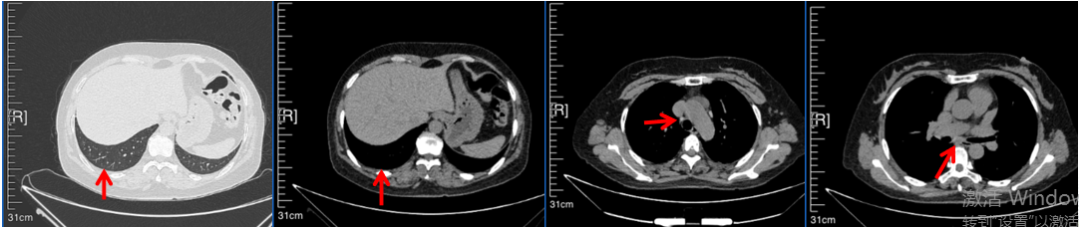

2016年1月复查CT提示支气管截断可见新发小结节,一线治疗采用培美曲塞+DDP方案化疗4周期(培美曲塞3.36,DDP 480mg)。化疗后复查胸部CT:右肺见不规则结节样影,最大层面大小约19mm*8mm,较前比较明显增大,疗效评估PD。2017.3-2017.4予单药多西他赛化疗3周期,疗效评估SD。2018年5月末复查CT提示结节较前增大,评效为PD,2018年6-10月予多西他赛+CBP化疗4周期,疗效评估SD。2022年5月患者出现活动后气短,复查胸部CT示右肺膨胀不良;右侧胸腔积液增多。胸腔积液包埋病理示符合肺腺癌细胞。行NGS基因检测:EML4:exon13-ALK:exon20融合。PD-L1(克隆号22C3)TPS<1%。

临床诊断:右肺上叶恶性肿瘤rT0N0M1a IVA期(第9版分期);恶性胸腔积液。

诊疗经过:2022年5月始口服克唑替尼3个月,出现肝功能异常(DILI 2级伴临床症状),改用恩沙替尼靶向治疗至今,目前评效为维持PR。恩沙替尼应用期间出现轻度肝功能异常(DILI 1级),对症处理后好转。截止目前PFS 33个月。

2024.12